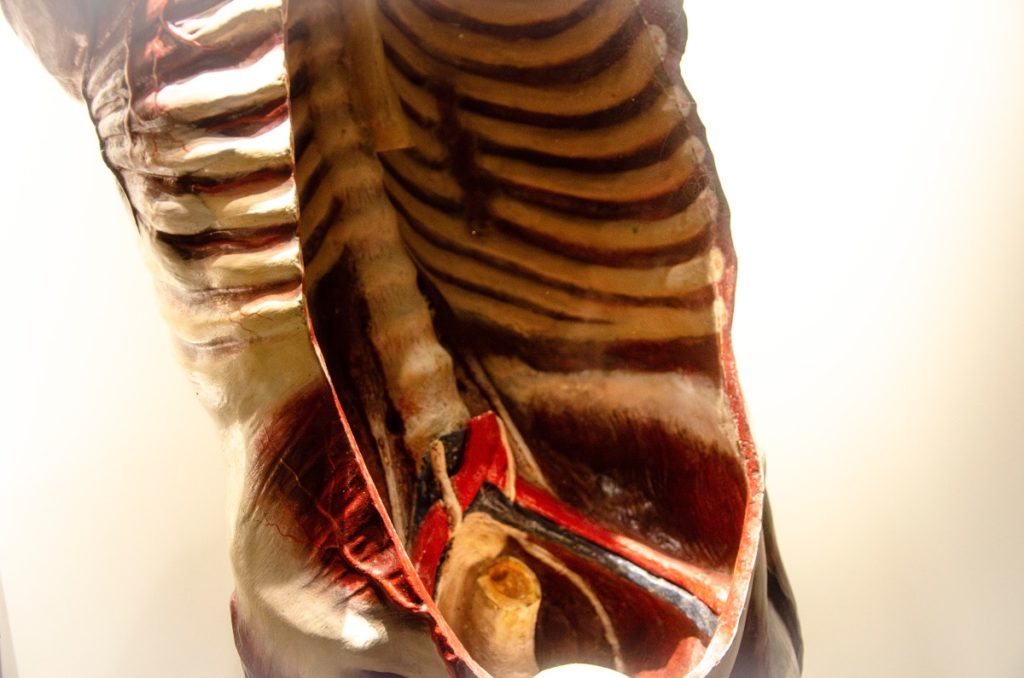

Modelos anatómicos y enseñanza científica

A comienzos del siglo XIX la descripción morfológica del cuerpo humano alcanza gran nivel de detalle. Se consolida el conocimiento anatómico como pilar imprescindible de la medicina científica. A partir de 1800, los modelos anatómicos empiezan a ser una herramienta valiosa para su correcta enseñanza.

Nuevos campos de estudio de la anatomía permiten a lo largo del siglo XIX comprender la realidad biológica de los seres vivos, progresando también la medicina científica. Y gracias a la popularización de los modelos, ese conocimiento puede llegar a los diferentes niveles de enseñanza.

La presencia de modelos de anatomia humana en los gabinetes Bergara está documentada ya en 1793. Los modelos que se han conservado hasta hoy son modelos más tardíos, de finales del XIX.

galeria de imagenes